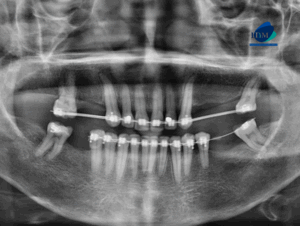

Paciente masculino de 22 años acude al Instituto de Dianóstico Maxilofacial para realizarse una tomografía macizofacial para la colocación de ortodoncia. A la evaluación de